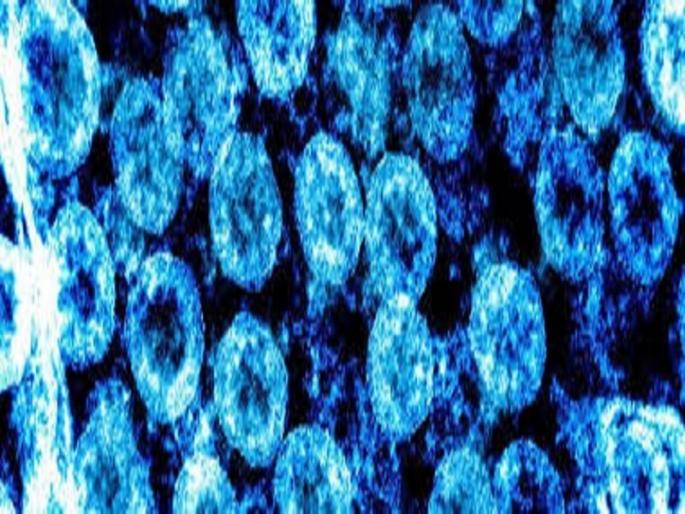

कोरोनाबाधितांचा आकडा अहमदनगरमध्ये वाढतच चालला आहे. आज गुरुवारी आणखी सहा जणांना कोरोनाची लागण झाल्याचे स्पष्ट झाले.  त्यामुळे अहमदनगरचा आकडा आता १४  वर पोहोचला आहे.

अहमदनगर : कोरोनाबाधितांचा आकडा अहमदनगरमध्ये वाढतच चालला आहे. आज गुरुवारी आणखी सहा जणांना कोरोनाची लागण झाल्याचे स्पष्ट झाले.

त्यामुळे अहमदनगरचा आकडा आता १४  वर पोहोचला आहे.

गुरुवारी (दि.२ एप्रिल) दुपारी ५१ जणांचा अहवाल पुण्याच्या एनआयव्हीकडून प्राप्त झाला. त्यात सहा जणांना कोरोनाची बाधा झाल्याचे स्पष्ट झाले. आणखी साठ ते सत्तर अहवाल येणे बाकी आहे. एकाच दिवशी सहा आकडा वाढण्याची ही पहिलीच वेळ आहे. त्यामुळे जिल्ह्यात आता मोठ्या प्रमाणावर खबरदारी घेण्याची गरज असून नागरिकांनी बाहेर पडू नये, अशा सूचना जिल्हा प्रशासनाने दिलेल्या आहेत.

दरम्यान यात दोन परदेशी, दोन नगर शहरातील मुकुंदनगर आणि दोन संगमनेर येथील नागरिकांचा समावेश आहे, अशी माहिती जिल्हा आरोग्य यंत्रणेने दिली आहे.